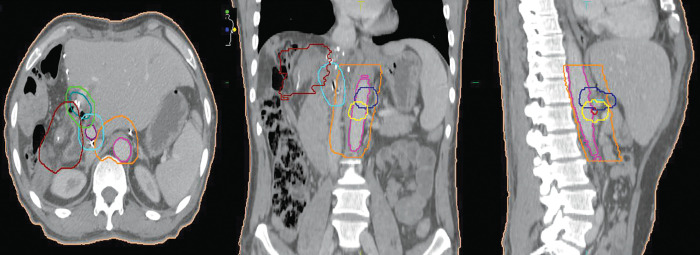

Materials and methods: For the present retrospective study, we identified 38 and 10 patients with resected perihilar and intrahepatic CCA. In perihilar CCA, adjuvant treatment was given as chemotherapy (n = 13) or chemoradiotherapy (n = 10). In intrahepatic CCA, neoadjuvant treatment was given with transarterial chemoembolization (TACE, n = 1) or chemotherapy plus stereotactic body radiation therapy (SBRT, n = 1), and adjuvant treatment was given to 7 patients with chemotherapy or chemoradiotherapy.

Results: In perihilar CCA, preoperative biliary drainage procedures were performed in 27 out of 30 patients with jaundice. The adjacent liver showed secondary sclerosing cholangitis (n = 5) and fibrosis (n = 19). Locoregional recurrence involved the hepaticojejunostomy anastomotic site and lymph nodes. In intrahepatic CCA, the adjacent liver revealed cirrhosis (n = 1), secondary sclerosing cholangitis (n = 1), and fibrosis (n = 6). The sites of recurrence were in the remnant liver and lymph nodes (n = 6). In perihilar CCA, the median overall survival (OS) and disease-free survival (DFS) rates were 30.1 months (95% CI: 22.9-37.4) and 15.1 months (95% CI: 9.74-20.5), respectively. The 2-year and 3-year OS were 60.5% and 44.7%, respectively. Multivariate analysis revealed a significant association of no adjuvant treatment with decreased DFS (p = 0.004), HR 4.03 (95% CI: 1.57-10.4). Recurrence showed an unfavorable association with OS (p = 0.056), HR 2.90 (95% CI: 0.98-8.66). In intrahepatic CCA, the median OS and DFS rates were 41.2 months (95% CI: 13.5-68.9) and 10.8 months (95% CI: 1.98-19.6), respectively. The 2-year and 3-year OS were 66.7% and 53.3%, respectively. The patient with multiple intrahepatic CCA lesions and treated with neoadjuvant chemotherapy and SBRT showed partial pathological necrosis after resection and was disease-free at 3.5 years.